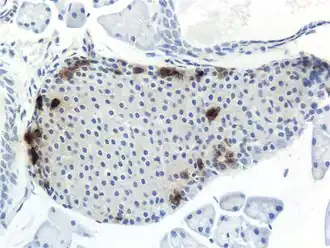

![]() Панкреатический островок мыши, ПП-клетки выделены. | |